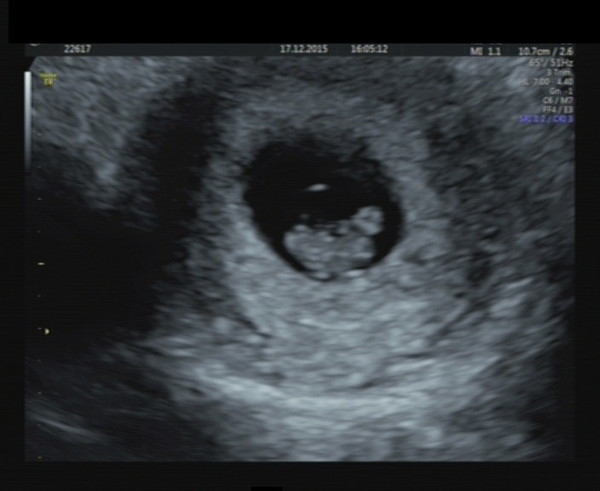

prettyflowers I had an early scan at 8 weeks at a place on Harley Street, we wanted reassurance so we could tell family at Christmas. The scan was great, they did it transabdominally (non invasive, which was nice!) and it picked up the heartbeat and showed the blob of baby, yolk sac etc. It was nice to see. I've uploaded a picture. The big blob is the baby, the small blob at the top right is the yolk sac. They sent us pictures and videos afterwards. Cant wait for the next scan now!